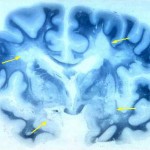

Perdita di memoria o morbo di Alzheimer? La salvia può aiutare nel trattamento di queste condizioni

Nel giugno 2003, la rivista, Pharmacology Biochemistry and Behavior , ha pubblicato alcuni risultati piuttosto rivelatori di una ricerca effettuata sulla salvia. Uno studio è stato condotto al fine di verificare il vero potenziale della pianta come un potenziatore della memoria. Gli scienziati hanno arruolato per la sperimentazione,  45 adulti osservati in  due processi separati. Alcuni individui hanno ricevuto un placebo, mentre altri sono stati trattati con estratto di olio essenziale ricavato dalla salvia , con dosi variabili tra 50 a 150 microls. Test di memoria sono stati eseguiti sui partecipanti, da 1 a 6 ore dopo l’assunzione. In ogni prova, anche le più piccole quantità di salvia sono  risultate utile ai partecipanti per migliorare notevolmente la loro memoria . Durante la Pharmaceutical Conference di Harrogate del 2003, il professor Peter Houghton ha presentato informazioni interessanti sulla ricerca che ha mostrato come la salvia  potrebbe contribuire a trattare il morbo di Alzheimer, o per lo meno, essere un’alternativa interessante ai farmaci usuali. Il dottor Houghton ha dimostrato come i composti attivi della salvia, simili a quelli impiegati in farmaci prescritti, erano capaci di neutralizzare la malattia di Alzheimer. Nell’esperimento, gli scienziati hanno scoperto che alcuni composti isolati da un estratto di salvia sono risultati essere AChE ( acetilcolinesterasi ) inibitori. Generalmente, il morbo di Alzheimer mostra un aumento di AChE che porta alla perdita di memoria mediante deplezione dei colinergici e non colinergici neuroni  del cervello . La salvia fornisce una buona opzione terapeuti per inibire ogni aumento di AchE  tanto quanto i farmaci inibitori.